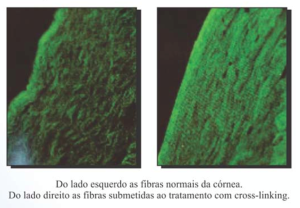

O procedimento “Cross-link ou Corneal Cross-Linking” consiste no uso de radiação ultravioleta, associada a uma substância chamada riboflavina, aumentando a rigidez biomecânica da Córnea. No Crosslinking ocorre o fortalecimento das fibras de colágeno, que representam as pontes de sustentação da Córnea. Com o aumento da resistência, diminui-se a elasticidade da córnea, reduzindo a chance de a progressão do Ceratocone.

Uma das principais causas do Ceratocone é a “fragilidade” do colágeno da Córnea.

Você sabe o que é Crosslinking? Segundo o especialista nesta cirurgia, Dr. Gustavo Bonfadini, o Crosslink de colágeno corneano (CXL) tem como finalidade criar novas ligações covalentes entre as moléculas de colágeno adjacentes, aumentando a resistência e a estabilidade da córnea e tem como finalidade impedir a progressão do Ceratocone. É uma técnica inovadora e revolucionária que veio para reduzir o número de Transplantes de Córnea.

Os estudos científicos demostram que o aumento na rigidez da Córnea possa ser de até 329%.